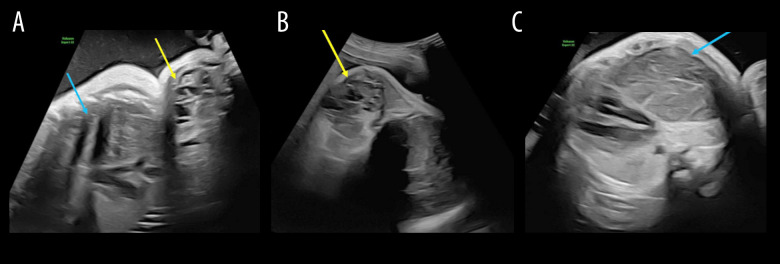

背景:在潜在的产后气道阻塞的情况下,宫内气管治疗(EXIT)是一项复杂的围产期手术。它需要一个经验丰富的多学科团队和基于胎儿成像的细致的手术计划。本报告描述了使用出口到气道的大宫颈畸胎瘤延伸到纵隔。病例报告:在妊娠35周时,一名29岁的女性因羊水过多来到我们的胎儿护理中心。胎儿随后被诊断为一个大的宫颈肿块延伸到纵隔。妊娠36周时进行出口至气道手术。在获得产后成像时,新生儿仍插管。在出生第3天,通过宫颈和纵隔联合入路切除畸胎瘤。病理证实为成熟畸胎瘤。新生儿的住院过程因吸入和喂养而变得复杂,需要胃造口管,她在出生第40天出院。结论:虽然宫颈畸胎瘤是EXIT手术的一个明确的适应症,但该病例因其妊娠晚期晚期的诊断和罕见的肿块延伸到纵隔,需要双重手术入路。它强调了在反复发生的晚期羊水过多的情况下维持广泛的鉴别诊断的重要性,并证明了多学科计划在预期气道损害时优化结果的关键作用。本病例提供了越来越多的证据,支持在复杂的颈纵隔肿块中扩大出口到气道的应用。

BACKGROUND Ex-utero intrapartum treatment (EXIT)-to-airway is a complex perinatal procedure performed in the case of potential postnatal airway obstruction. It requires an experienced multidisciplinary team and meticulous surgical planning based on fetal imaging. This report describes the use of EXIT-to-airway for a large cervical teratoma with extension into the mediastinum. CASE REPORT At 35 weeks' gestation, a 29-year-old woman presented to our fetal care center with significant polyhydramnios. The fetus was subsequently diagnosed with a large cervical mass extending into the mediastinum. An EXIT-to-airway procedure was performed at 36 weeks' gestation. The neonate remained intubated while postnatal imaging was obtained. At day of life 3, resection of the teratoma was performed via a combined cervical and mediastinal approach. Pathology confirmed a mature teratoma. The neonate's hospital course was complicated by aspiration with feeding, requiring a gastrostomy tube, and she was discharged on day of life 40. CONCLUSIONS While cervical teratoma is a well-established indication for the EXIT procedure, this case is notable for its late third-trimester diagnosis and the rare extension of the mass into the mediastinum, which necessitated a dual surgical approach. It highlights the importance of maintaining a broad differential diagnosis in the setting of recurrent third-trimester polyhydramnios and demonstrates the critical role of multidisciplinary planning in optimizing outcomes when airway compromise is anticipated. This case contributes to the growing body of evidence supporting the expanded utility of EXIT-to-airway for complex cervicomediastinal masses.